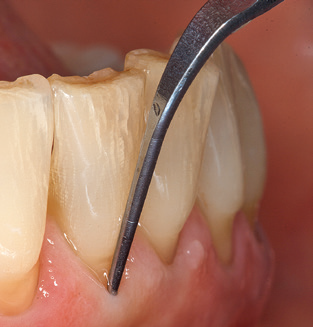

Fig. 4: Flexible probes with millimetre markings are recommended for the probing of dental implants (e.g. Colorvue Kit PCV11KIT6, Hu­Friedy). – Fig. 5a and b: A straight working tip (1P, W&H Dentalwerk Bürmoos GmbH) is a suitable instrument for use on all natural teeth. – Fig. 6: Curved working tips (3Pr/3Pl, W&H Dentalwerk Bürmoos GmbH) lend themselves to the processing of difficult-to-reach areas of the tooth and root surfaces (e.g. furcations). – Fig. 7: The tapered, hexagonal implant cleaning tip (1I, W&H Dentalwerk Bürmoos GmbH) permits atraumatic and efficient cleaning of the crown and abutment surfaces. – Fig. 8: Titanium and carbon curettes are suitable instruments for the manual cleaning of the implant surfaces.

Good illumination of the working field facilitates the process considerably. The system used by the authors achieves this thanks to a 5x LED ring integrated in the handpiece. Naturally, a range of working tips for different indications is also offered. A straight, universally employable tip is the basic instrument required for machine cleaning of natural teeth (Fig. 5a and b). Curved tips, which allow access to exposed furcations, are also available for hard-to-reach areas in the posterior region (Fig. 6).

Of course, working tips for the cleaning of implant surfaces are also indispensable for SPT in patients fitted with implants. The implant cleaning attachment on the system used here is characterised by its tapered, hexagonal design. This design allows light, atraumatic penetration of the peri-implant pocket and displays a good cleaning performance (Fig. 7).